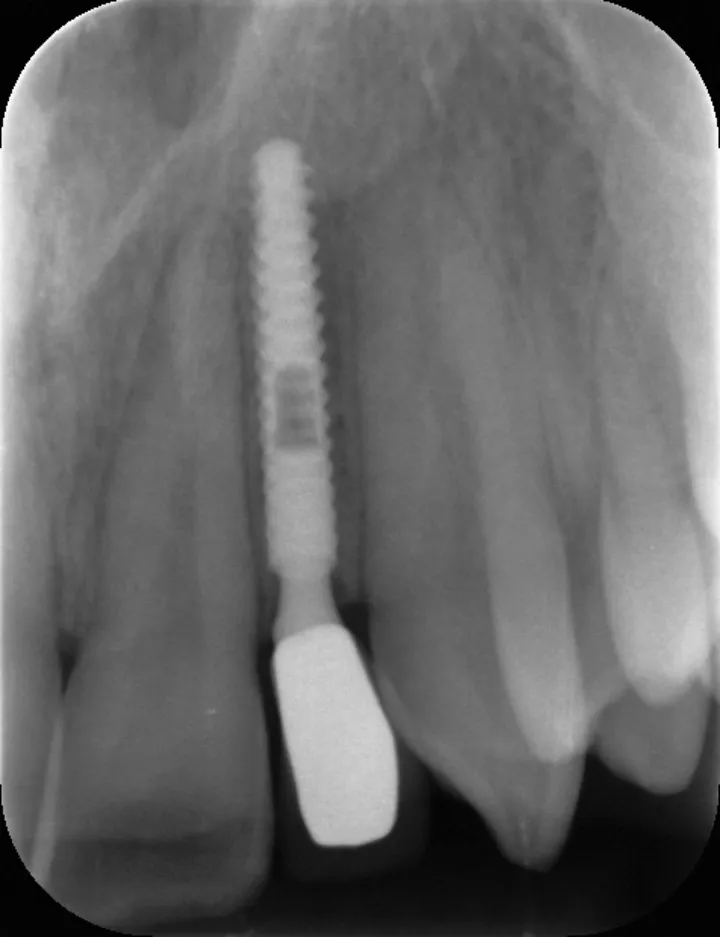

由一名独立评估人员使用 Kinovea 软件对骨组织水平进行了 X 线测量,测量结果用种植体实际长度进行校准(图 2)。研究开始时测量的骨组织水平(首次种植术时骨水平)与种植术后 1 年时测量的骨组织水平之差即为骨吸收。

平均骨组织水平经近中和远中水平值计算得出。

最常用的种植体长度为 14mm(图 3 和图 4);66% 的冠修复采用烤瓷熔附金属全冠,34% 采用全瓷冠。

图2:术后 1 年近、远中骨组织水平测量值。

六颗种植体出现 0 至 1 mm 的骨吸收。一颗种植体的骨吸收超过 2mm(表 1)